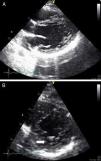

Monitorizada em ambiente de unidade de cuidados intensivos cardíacos, realizou ecocardiograma, que revelou ventrículo esquerdo de dimensões normais com fracção de ejecção do ventrículo esquerdo (FEVE) global ligeiramente deprimida (FEVE ± 45%) e imagens compatíveis com VENC a nível apical (trabeculações exuberantes com relação camada trabeculada/não trabeculada superior a dois e com fluxo detetado por Doppler de cor ao nível das mesmas) (Figuras 4 e 5). Foi efetuada coronariografia, revelando ausência de doença coronária.